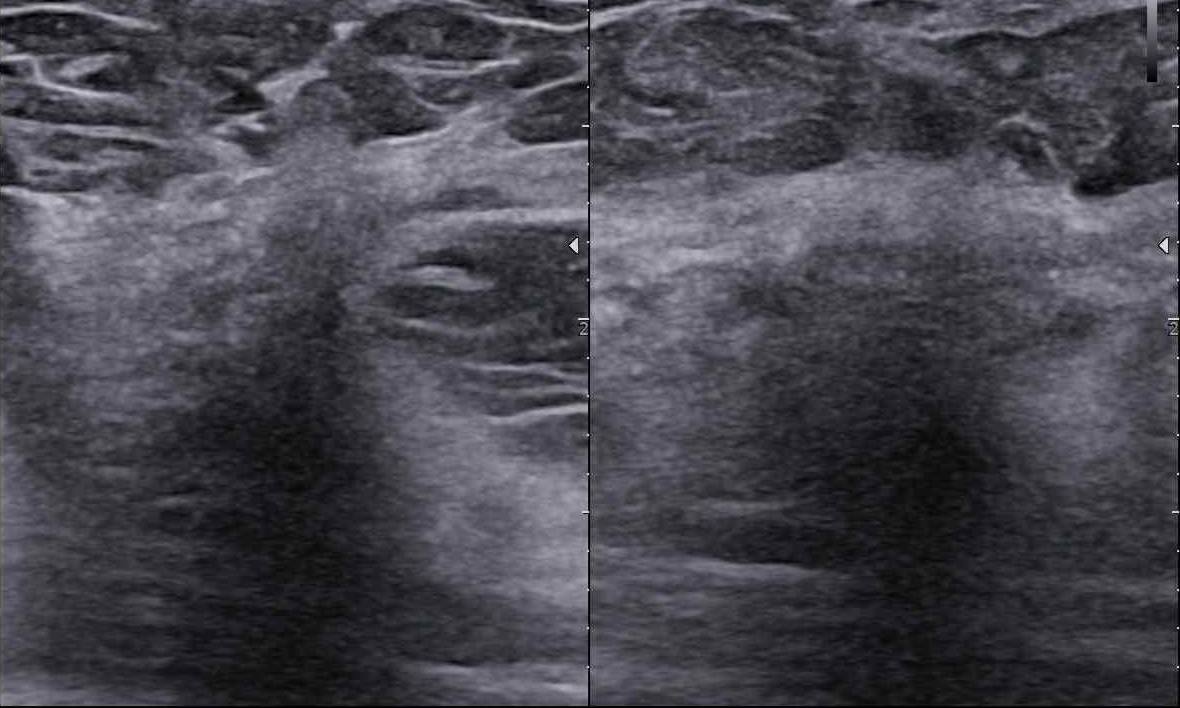

Czy podział BIRADS 4 ma sens? Jak radzić sobie  z BIRADS 4a, b, c?

Czy my rzeczywiście potrafimy czytać tę skalę? Dlaczego tyle jest rozbieżności?